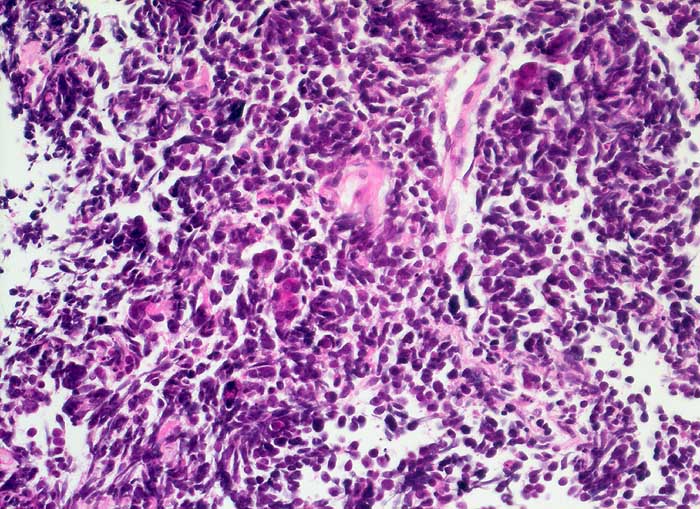

n/ Kleinzelliges Bronchuskarzinom

Kleinzelliges Bronchuskarzinom

Der Nachweis des kleinzelligen Karzinoms gelingt im Sputum meist leichter als im Bronchialsekret. Im Bronchialsekret sind die Tumorzellen oft zwischen Flimmerzellen und Entzündungszellen versteckt, während die stark hyperchromatischen Kerne im Sputum schon bei schwacher Vergrösserung ins Auge fallen. Die fast nacktkernigen Zellen liegen einzeln oder bilden schmale zeilenförmige Verbände und Haufen. Innerhalb der Verbände schmiegen sich die Kerne eng aneinander (=molding). Die Kerne sind zwei- bis dreimal so gross wie Lymphozyten. Im Sputum erscheinen die Karzinomzellen kleiner als im Feinnadelpunktat, Bürstenabstrich oder Bronchialsekret.

Basalzellen sind monomorpher und bilden kleine, regelmässige kompakte Verbände. Lymphomzellen liegen stets einzeln. Feindisperse Chromatinverteilung und zeilenförmige Verbände sprechen gegen ein Lymphom. In Zweifelsfällen erfolgt die Unterscheidung immunzytochemisch (Panzytokeratin und CD45).

Das ersten Beispiel zeigt ein Bronchialsekret, das zweite eine Bronchialbürstenzytologie.